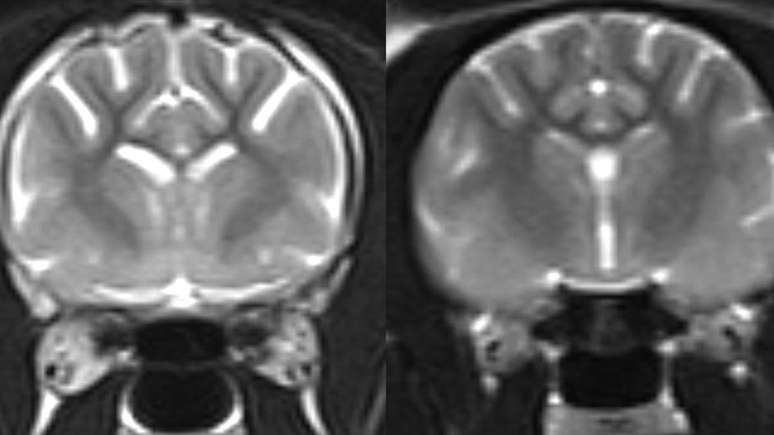

As áreas claras na imagem de ressonância magnética à esquerda mostram maior perda de tecido cerebral em um gato vivo com demência, em comparação com um cérebro felino normal, mostrado à direita